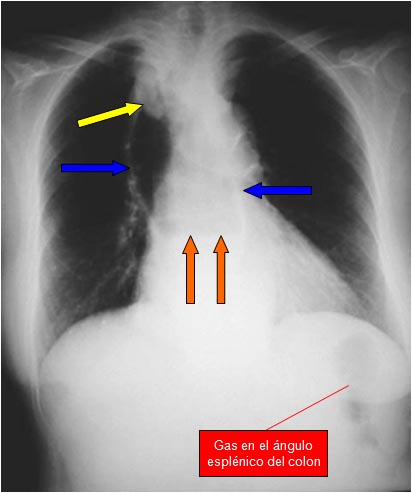

SIGNO DEL GRANO DE CAFÉ

Signo de obstrucción intestinal con estrangulación (vólvulo, hernia incarcerada,…), que provoca obstrucción simultánea a dos niveles -asa cerrada-. El asa afecta, llena de aire y doblada sobre sí misma, adquiere el aspecto de un grano de café con una banda central densa que corresponde a las paredes opuestas del asa estrangulada. Cuando la radiografía es en bipedestación puede aparecer un nivel hidroaéreo en cada segmento del intestino dilatado.

La fotografía corresponde a un paciente con vólvulo de sigma. Suele ser habitual en pacientes con vólvulo de sigma que el grano de café ocupe casi todo el abdomen. Hasta un 80 % de estos vólvulos se diagnostican solo con la radiografía de abdomen en decúbito. La ausencia de gas rectal contribuye a reforzar el diagnóstico.

El signo también ha sido descrito en obstrucciones en asa cerrada de intestino delgado, pero lo más habitual es que se aplique al vólvulo de sigma.

El Signo del grano de café también se ha llamado Signo de la U invertida y Signo del tubo doblado

SIGNO DE LA LÍNEA BLANCA

En la imagen del signo anterior también es visible el Signo de la línea blanca, formada por las paredes del sigma dilatado próximas entre sí, es decir, corresponde a la línea que divide en dos el «grano de café».

SIGNO DE LAS LÍNEAS CONVERGENTES

Es un signo de vólvulo de sigma que se ve al tiempo que el Signo del grano de café, pero no referido al luminograma del sigma dilatado sino a las paredes sigmoideas. Se trata de tres líneas que delimitan la pared del sigma (flechas), dos laterales y una central, más gruesa, formada por la aposición de las paredes de las dos partes del sigma, la que asciende y la que desciende. Las tres líneas convergen en la pelvis en la zona de la volvulación.